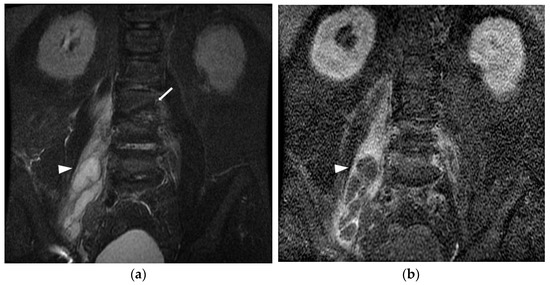

Each patient received intravenous antibiotics once IPA was diagnosed. Eighty-eight (50%) patients underwent PCD, 32 (18.2%) patients underwent surgical debridement, and 56 (31.8%) patients received antibiotics alone. Overall, 81 (46.0%) patients received primary antibiotic treatment. Of these patients, 50 survived hospitalizations without an interventional procedure, six passed away, and 25 failed the initial antibiotic treatment with additional intervention. The failure rate of antibiotics-only treatment was 38.3% (31/81). Ninety (51.1%) patients underwent primary PCD, of whom 65 survived, five passed away, and 20 failed PCD with additional salvage surgery. The failure rate of primary PCD was 27.8% (25/90). In contrast, five patients underwent primary surgical debridement, and all of them survived with a failure rate of 0% (0/6) (Figure 2). When the abscess diameter was larger than 8cm, primary PCD or surgery was significantly more frequently performed than primary antibiotics in patients with IPA (41.7% vs. 19.6%, p = 0.004). Among all the patients with IPA, 86 (48.9%) and 30 (17%) patients presented with sepsis and septic shock, with the percentage being significantly higher in the non-survivors than in the survivors (100% vs. 44.8%, p < 0.001; 92.3 vs. 11%, p < 0.001). The mean LOS was 32.4 ± 26.9 days. There were 38 (21.6%) patients admitted to the intensive care units, and 13 (7.4%) passed away during hospitalization (Table 4). During a median follow-up period of 9.4 months (IQR: 3.0–28.3), 34 out of 176 patients (19.2%) experienced recurrent IPAs. Among them, the median time to recurrence was 76 days (IQR: 51–196) after the diagnosis of index IPA.

Figure 2. Treatment outcomes with primary antibiotics, percutaneous drainage, and operation in patients with iliopsoas abscess. ABX: antibiotics; PCD: percutaneous drainage; OP: operation.